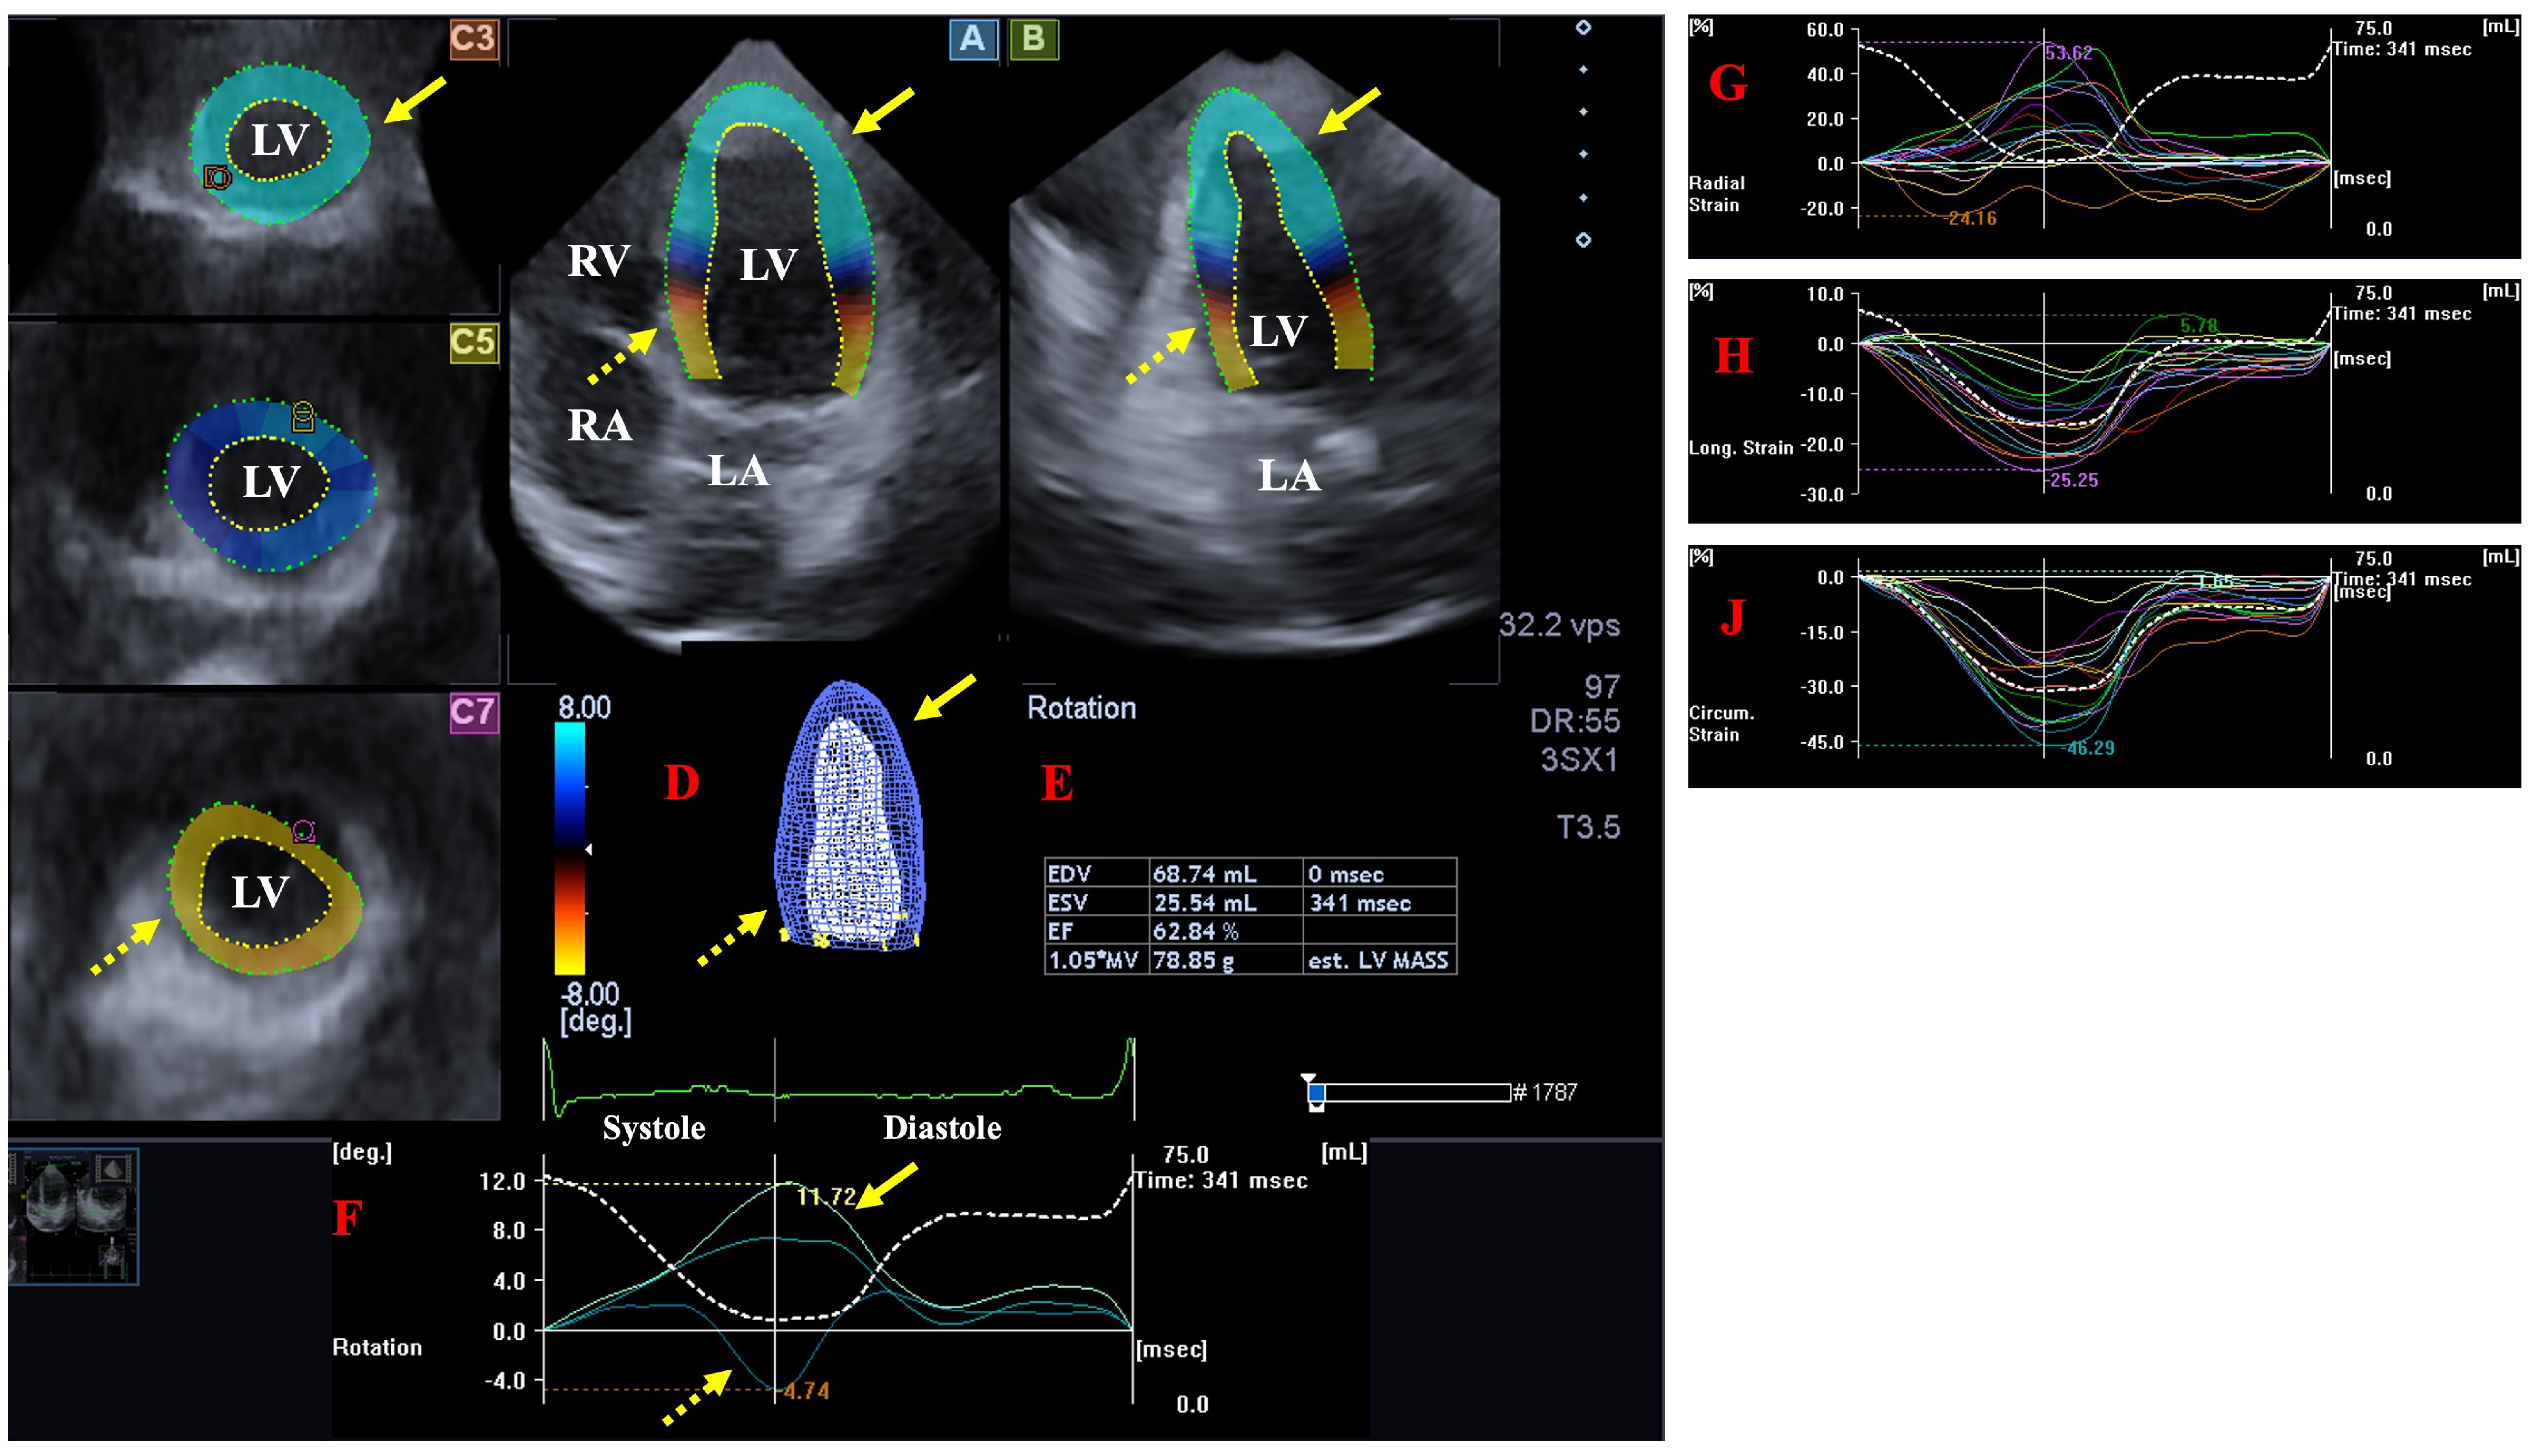

- The following LV rotational parameters were provided: apical and basal LV rotations, LV twist and time-to-peak LV twist [25].

- The following global LV strains, featuring the whole LV were measured [26]:- ○

- LV radial strain (LV-gRS)—for characterizing thinning/thickening of the myocardial tissue.

- LV longitudinal strain (LV-gLS)—for characterizing lengthening/shortening of the myocardial tissue.

- LV circumferential strain (LV-gCS)—for characterizing widening/narrowing of the myocardial tissue.